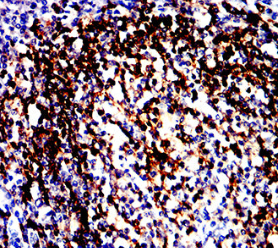

IHC    1/200 - 1/1000